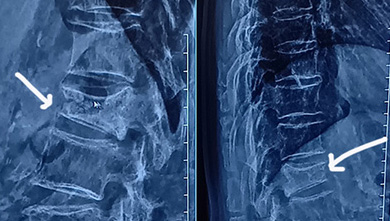

昨日 ママリンの病院だったの~前回から3週間経ったかな?もう痛みはないし コルセットちょっとぐらい外したいみたいなこと言ってたんだけどレントゲン見たら 全然良くなってなかったよ(つд⊂)痛みがなくなったのは ぎっくり腰が治っただけで骨折の痛みじゃなかったからってかんじ?前回はレントゲンちらっと見ただけでよくわかんなかったので今回はスマホで写真撮ってきた左が8月で右側が7月こうやってみると本当につぶれてる(;'∀')骨折したときのレントゲンそんなに鮮明じゃなかったからあんまりつぶれてないんじゃないぐらいに思ってたの右側が6月ので、地方の病院のレントゲン写真です鮮明じゃないからわかんないよね?ママリンがもう痛くないっていうから楽観視してたけどまだ骨が固まってきてないみたいなのでとりあえずこのまま固定して様子見るけど 違う方向からもアプローチするかも?この日の午後に骨密度検査も予定してたのでその結果と 血液検査もして 2週間後ぐらいには結果が出るからその時にまた診察してもらうことになった~骨密度が低かったら お薬で治療するとかもあるだろうしとりあえず今後も 骨折したときにどんな食事がいいかっていうのを色々調べて食べさせていきたいと思います骨折を早く治すためには、カルシウム、ビタミンD、ビタミンK、タンパク質をバランスよく摂取することが大切です。これらの栄養素は、骨の形成や修復を助ける働きがあります。また、過度なアルコールやカフェインの摂取はカルシウムの吸収を妨げるため、注意が必要ですってことなので一応 乳製品とかタンパク質とかは積極的に摂らせてたけどもうちょっとちゃんとやりますカフェインの摂取が多かったかもしれないので それ控えなきゃ(;'∀')コーヒーとか紅茶とか飲んでたから-----------------------カルシウム 強い骨を作る牛乳 ヨーグルトなどの乳製品 小魚大豆 大豆製品などビタミンD カルシウムの吸収をサポート青魚 キノコ類 日光浴ビタミンK 骨代謝を整える納豆 緑黄色野菜などヨーグルトは毎朝食べてる最近は豆乳を買ってきてそれ飲むように促してる日光浴がてらウォーキングもしなきゃね納豆は買ってきた!緑黄色野菜ってことで サラダの時はブロッコリーいれたり和食の時は小松菜とか使ったりかな?朝病院へ行って 診察してもらって一旦家に帰ってお昼作って食べたときの写真会計は午後骨密度検査終わってからだったのでスタバでお茶はしなかったんだけどテイクアウトしてきたこの間売切れてたピーチソーダとピーチティーですご飯は 昨日の残り物のプルコギをパニーニにしました低糖質ブレッドにプルコギのせる牛肉、パプリカ、マイタケ、ネギつかったかな?それにチーズ乗せて マヨ乗せて焼きましたチーズでカルシウムも補ってみたバランスよくサラダもつけました♪この後ちょっと休憩して 15時にまた病院へ~30分前に行ったけど(笑)朝はめっちゃ待たされたのよ 8時すぎぐらいに出てレントゲン8時半に終わって 診察が9時の予定なのに 全然呼ばれないの10時になっても呼ばれないわたして順間違えた? ってバーコードで受付確認する機械があるのでもう一度やろうと思って行ったら 職員が隣に立ってたので 全然呼ばれないんですけど~って言ってみたら 先生に聞いてみますねってそしたら次に呼ばれたのよ(;'∀')なんなの? 我慢しないでもっと早く言えばよかったかも~前回も 9時前には受付すんでたのに 全然呼ばれなくて後から来た人がどんどん呼ばれていく どんな順番になってんの?って思ってたのよ9時の予定なのに モニター見たら9時半の予約のところを見てるみたいな表示があって明らかにおかしいなって思ってたら その時はいう前に呼ばれたので言わなかったけど。。。次は30分以上過ぎたら言うようにしよっと!待ち疲れちゃったもん┐( ̄ヘ ̄)┌ フゥゥ~ママリンもずーっとベンチに座ってて疲れちゃったみたいだしんで骨密度検査は30分前に行ったら 誰も待ってなくて1番だったので予定よりも早く呼ばれて 検査してもらい会計のところへ行って受付したら 15時前に全部終わっちゃいました(笑)ってことで午後はスタバでお茶(笑)いつも会計待ちでスタバ寄ってるんだけど席が空いたのでママリンに座らせて 注文し終わってなんとなく会計の順番見てたら<=これもモニターに表示されるもう番号が来てたので セルフで会計も終わらせられちゃったのだお茶する前に(* >ω<)=3 プーでも注文しちゃったからお茶~ママリンはほうじ茶ラテだよとにかく疲れた一日でした┐( ̄ヘ ̄)┌ フゥゥ~